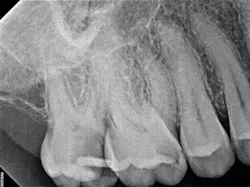

The iTero scanner was able to clearly define the delineation between the soft and hard tissue as can be seen in this image of the digital die trim (figure 3). Radiographs were captured on delivery revealing a clinically acceptable outcome for the patient (figure 4). Direct restorations were completed on teeth Nos. 3 and 4 during this visit.